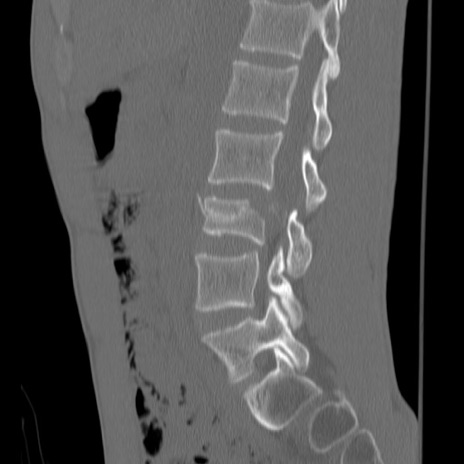

症例3 腰椎CT(矢状断像)

【症例】30歳代男性

【主訴】腰痛

【現病歴】本日旅行先で観光中に、友人と衝突し転倒し受傷。

【身体所見】麻痺なし、右下腿内側前面外側、左下腿内側に知覚鈍麻・しびれ

異常所見と診断は?

腰椎CT